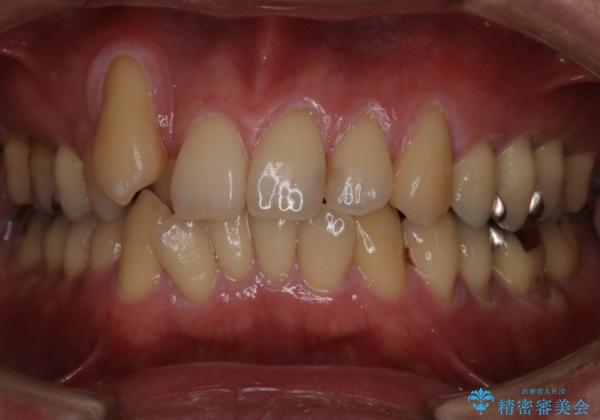

- 右上2番目の歯が舌側転位していることと前歯の叢生(がたつき)を主訴に来院されました。

右上の犬歯が初診時よりかなり歯根露出しており、矯正の力をかけるとさらに歯根露出するリスクがあるため、右上の2番目の歯を前に出すためにも

右上の犬歯を抜歯して歯並びを整える治療計画を立てました。

下のがたつきをとるために、IPR(歯と歯の間を削る処置)も行って歯を並べていきます。

抜歯の本数を最小限に抑えたことで、治療計画も1年5ヶ月と短期間で終了することができ

主訴である前歯のがたつきも改善され綺麗な歯並びになりました。

矯正の装置を除去したタイミングで、ホワイトニングも行うことで歯の色味も白くなりました。